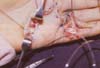

Las maniobras a ciegas en el canal digital producen lesiones que inducen adherencias, que pueden influir negativamente en el deslizamiento final de los tendones; por esta razón se debe identificar la ubicación de los extremos tendinosos y acercarlos en una forma atraumática utilizando ayudas como sondas para acercarlos, contrain-cisiones y agujas para fijarlos y poder realizar una tenorrafia sin tensión. (Figuras 2 y 3).

Fig. 2. Recuperación del muñón proximal del tendón de la palma con sonda en lesión de la zona 2.

Fig. 3. Afrontamiento de los extremos tendinosos para la sutura